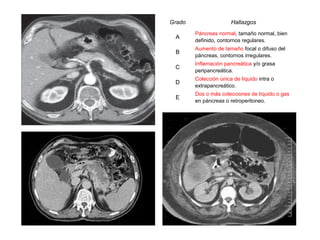

CRITERIOS TOMOGRÁFICOS DE [EMIL] BALTHAZAR

Grado                Hallazgos                 Puntos              Puntuación             Mortalidad

necrosis                severidad

Páncreas normal, tamaño normal,

A                                              0         0           0            0

bien definido, contornos regulares.

Aumento de tamaño focal o difuso

B                                              1         0           0            1

del páncreas, contornos irregulares.

Inflamación pancreática y/o grasa

C                                              2       < 33          2            4

peripancreática.

Colección única de líquido intra o

D                                              3       33-50         4            7       > 17 %

extrapancreático.

Dos o más colecciones de líquido o

E                                              4       > 50          6           10

gas en páncreas o retroperitoneo.

Se considera como Pancreatitis Aguda severa a toda Pancreatitis Aguda con índice de

severidad de 6 puntos o más y/o un Balthazar D - E.

La tomografía abdominal dinámica contrastada es el "Gold standard" o "Regla de Oro"

para el diagnóstico clínico de la Pancreatitis Aguda.

Grado                  Hallazgos

Páncreas normal, tamaño normal, bien

A

definido, contornos regulares.

Aumento de tamaño focal o difuso del

B

páncreas, contornos irregulares.

C

D

Dos o más colecciones de líquido o gas

E

en páncreas o retroperitoneo.